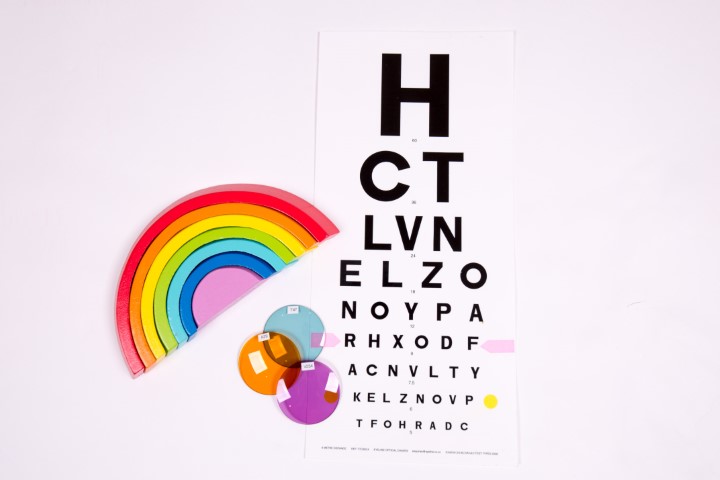

How to tell if Irlen syndrome might be part of the problem

Irlen specs: the coloured-lenses help with visual processing

Over 100 scientific studies on the topic have established a hereditary component of the disorder1-3, a number of biochemical markers for problems associated with Irlen Syndrome4-6, and differences in brain function between individuals with and without the condition7-11. Precision-tinted colored filters have been found to normalise abnormal brain activity and eliminate issues with print clarity and stability, physical symptoms, and light sensitivity associated with the condition12-21. Although originally thought to be associated solely with reading problems, research has linked visual processing difficulties to a range of other disorders, including ADHD (attention deficit hyperactivity disorder), ASD (autism spectrum disorders), learning disabilities, anxiety and certain emotional and psychological issues22-24. Visual processing challenges also overlap with other neurological conditions, such as migraines and tourette’s8, 25.